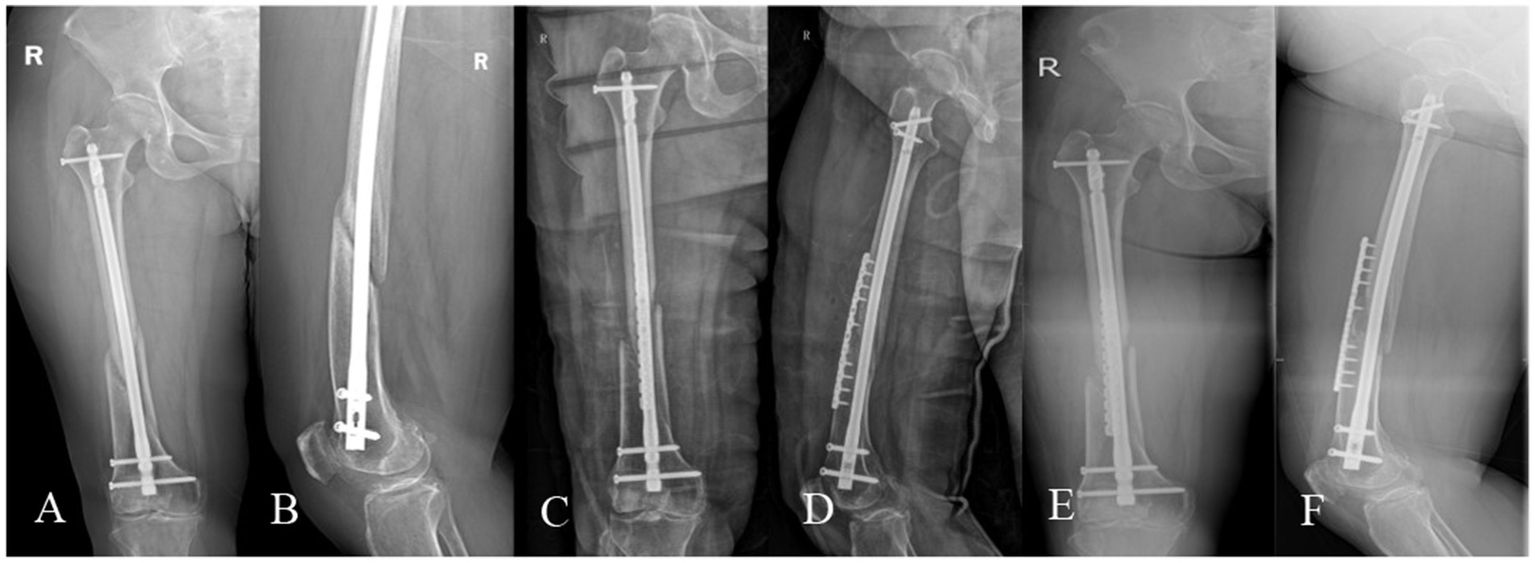

A 39-year-old male, BMI: 22.16 kg/m2, non-smoker, no metabolic diseases. (A,B) Right femoral shaft fracture sustained in a car accident on January 5, 2021. (C,D) Closed reduction and intramedullary nailing performed on January 13, 2021. (E,F) Nonunion with minimal callus formation observed during follow-up on October 8, 2021. (G,H) Revision surgery on October 23, 2021, retaining the original nail and augmenting with autologous iliac cancellous bone grafting and an auxiliary plate. (I,J) Persistent nonunion noted during follow-up on July 7, 2022. (K,L) Second revision surgery on July 12, 2022, utilizing dual locking plate fixation, PRP-augmented structural iliac bone grafting, and bioactive core construction. (M,N) Excellent radiographic union observed at 6.2 months postoperatively, with a lower extremity functional score of 65 and a VAS pain score of 1.

From 98 initially reviewed medical records, 45 cases were excluded: 25 lacking dual plate fixation, 7 without PRP application, 5 without autologous iliac grafting, 5 infected nonunions, 2 segmental bone defects, and 1 incomplete documentation. Of the 53 included patients, one died in a traffic accident at 5.2 months postoperatively, leaving 52 final participants (35 males, 17 females; mean age 41.38 ± 13.95 years, range 18–69). Nonunion classifications included hypertrophic (19, 36.5%), atrophic (26, 50%), and oligotrophic (7, 13.5%), with 33 femoral shaft (63.5%) and 19 supracondylar (36.5%) cases. All patients completed follow-up (mean 19.01 ± 6.69 months, range 12–45). Baseline characteristics—including interval between initial and revision surgery, injury mechanism, anatomical location, and prior fixation methods—are detailed in Table 1. All 52 patients achieved union (Table 2), with a mean time to clinical and radiographic union of 6.56 ± 1.04 months (range 5–10.3). At 9-month follow-up, 50 patients (96.2%) met union criteria; all achieved union by final follow-up (100%). Representative cases are shown in Figures 3, 4. At initial union confirmation, mean visual analog scale (VAS) pain score was 0.63 ± 0.97 (range 0–5), lower extremity functional score (LEFS) averaged 63.92 ± 5.92 (range 52–76), and thigh incision healing time was 12.13 ± 1.36 days (range 10–16). Postoperatively, 5 patients (9.62%) had complications: 2 donor site discomforts after exercise, 1 femoral vein thrombosis, 1 chronic knee pain (VAS 5), and 1 delayed thigh incision healing (healed day 16). No hematoma or heterotopic ossification occurred. Two patients (3.85%) had serious complications: 1 femoral vein thrombosis (resolved with 1 month oral rivaroxaban) and 1 chronic knee pain (improved with oral diclofenac and topical flurbiprofen gel).

Femoral fracture nonunion, a complication with profound functional implications (2, 3), lacks consensus on optimal management despite numerous reported strategies, with conflicting success rates across methods (5–8). Our protocol—combining dual locking plate fixation for biomechanical stability, PRP-augmented autologous iliac bone grafting, and bioactive core construction—achieved 100% union rates, accelerated healing (mean 6.56 months), excellent pain control (mean VAS 0.63), and functional recovery (mean LEFS 63.92), enabling early rehabilitation. Representative cases are shown in Figures 3, 4.